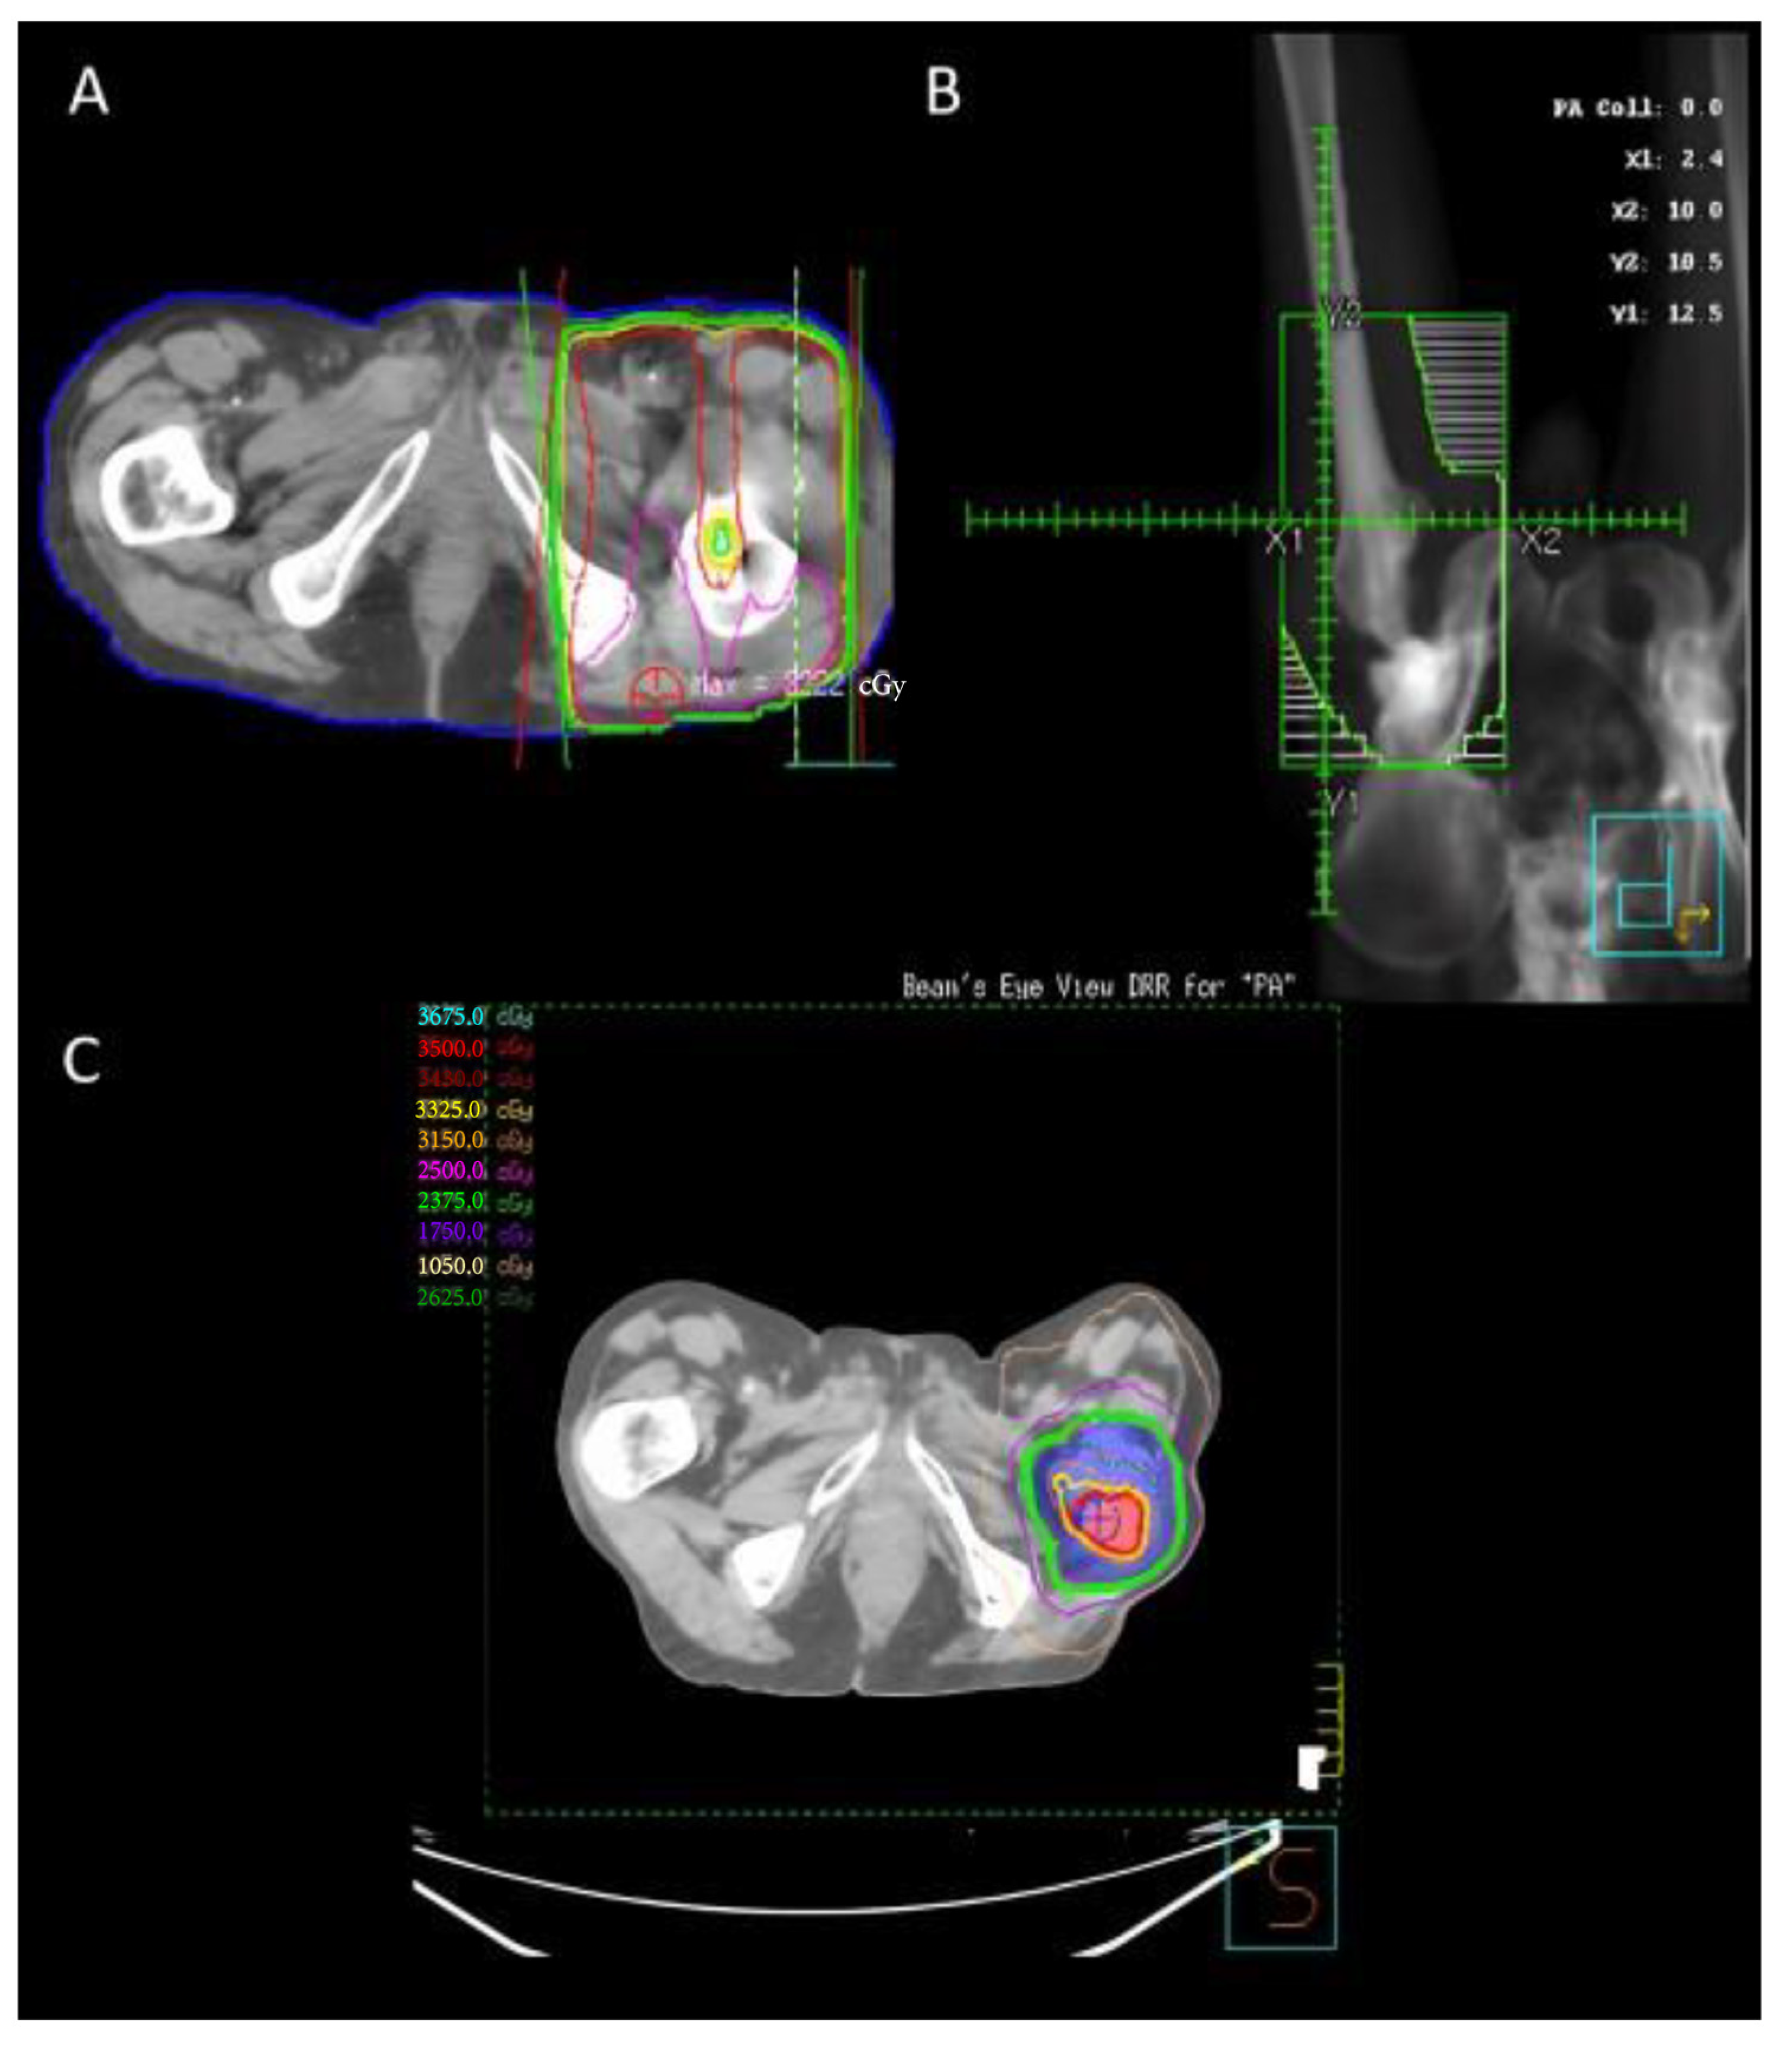

2.9. Clinical Example